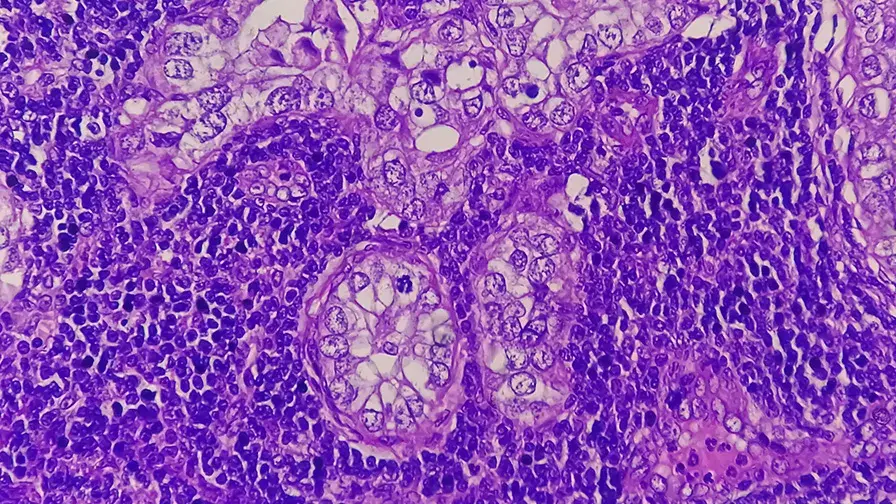

• Adénocarcinome de l’estomac, vue microscopique

© Getty Images